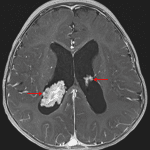

- Frondlike avidly enhancing lesions in the bilateral lateral ventricles associated with the choroid plexus

- The right lateral ventricular lesion is larger and measures 3.2 x 2 x 3.5 cm

- These lesions are isointense on T1 and T2 and do not demonstrate corresponding susceptibility artifact or restricted diffusion

- Generalized enlargement of the lateral and third ventricles, and to a lesser extent of the fourth ventricle, suggestive of communicating hydrocephalus

Choroid villous hyperplasia vs choroid plexus papillomas